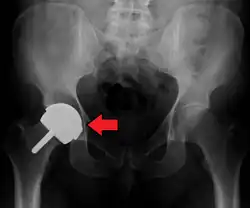

Intraoperative acetabular fracture

Intraoperative fractures may occur. After surgery, bones with internal fixation devices in situ are at risk of periprosthetic fractures at the end of the implant, an area of relative mechanical stress. Post-operative femoral fractures are graded by the Vancouver classification.[32][33]